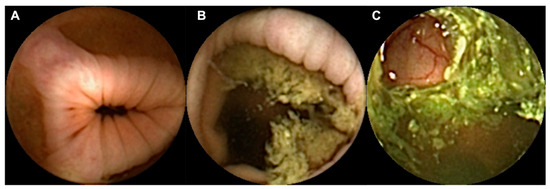

2.3. Classification of Bowel Preparation